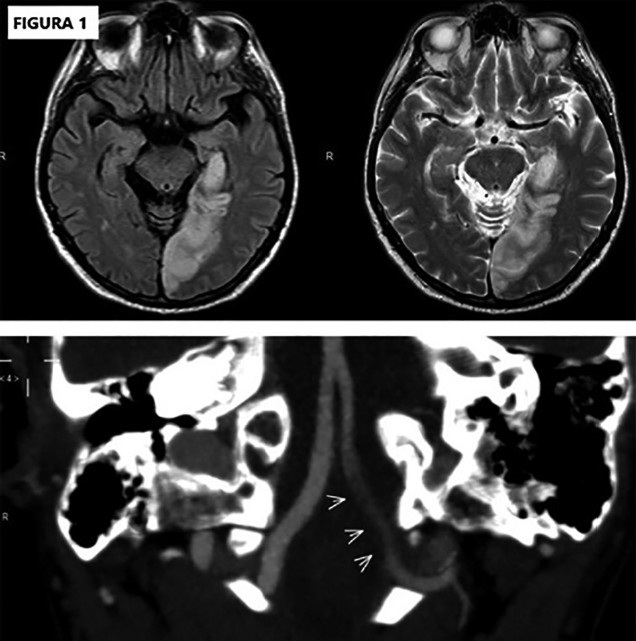

Se presenta un varón de 59 años, extabaquista (40 pack/year), hipertenso y dislipidémico, que presentó un trastorno de la marcha de 2 semanas de evolución y relató un registro de hipotensión arterial en el miembro superior izquierdo. En consulta con su médico laboral se constató afasia de expresión, hemianopsia temporal derecha e inestabilidad de la marcha, y se decidió su internación. En el electrocardiograma se constató ritmo sinusal; en el ecocardiograma, función sistólica ventricular izquierda conservada, sin shunt intracavitario ni trombos intraluminales. En el eco Doppler de vasos de cuello: ateromas subintimales carotídeos sin hallazgos hemodinámicamente significativos, con flujo de muy baja velocidad en la arteria vertebral izquierda. La tomografía axial computada (TAC) de cerebro reveló áreas hipodensas en la sustancia blanca bifrontoparietales. La angioresonancia magnética nuclear de cerebro evidenció una lesión isquémica aguda temporo-occipital izquierda en territorio de la arteria cerebral posterior izquierda, con ausencia de flujo en el segmento intracraneal de la arterial vertebral. (Figura 1)

RMN: resonancia magnética nuclear